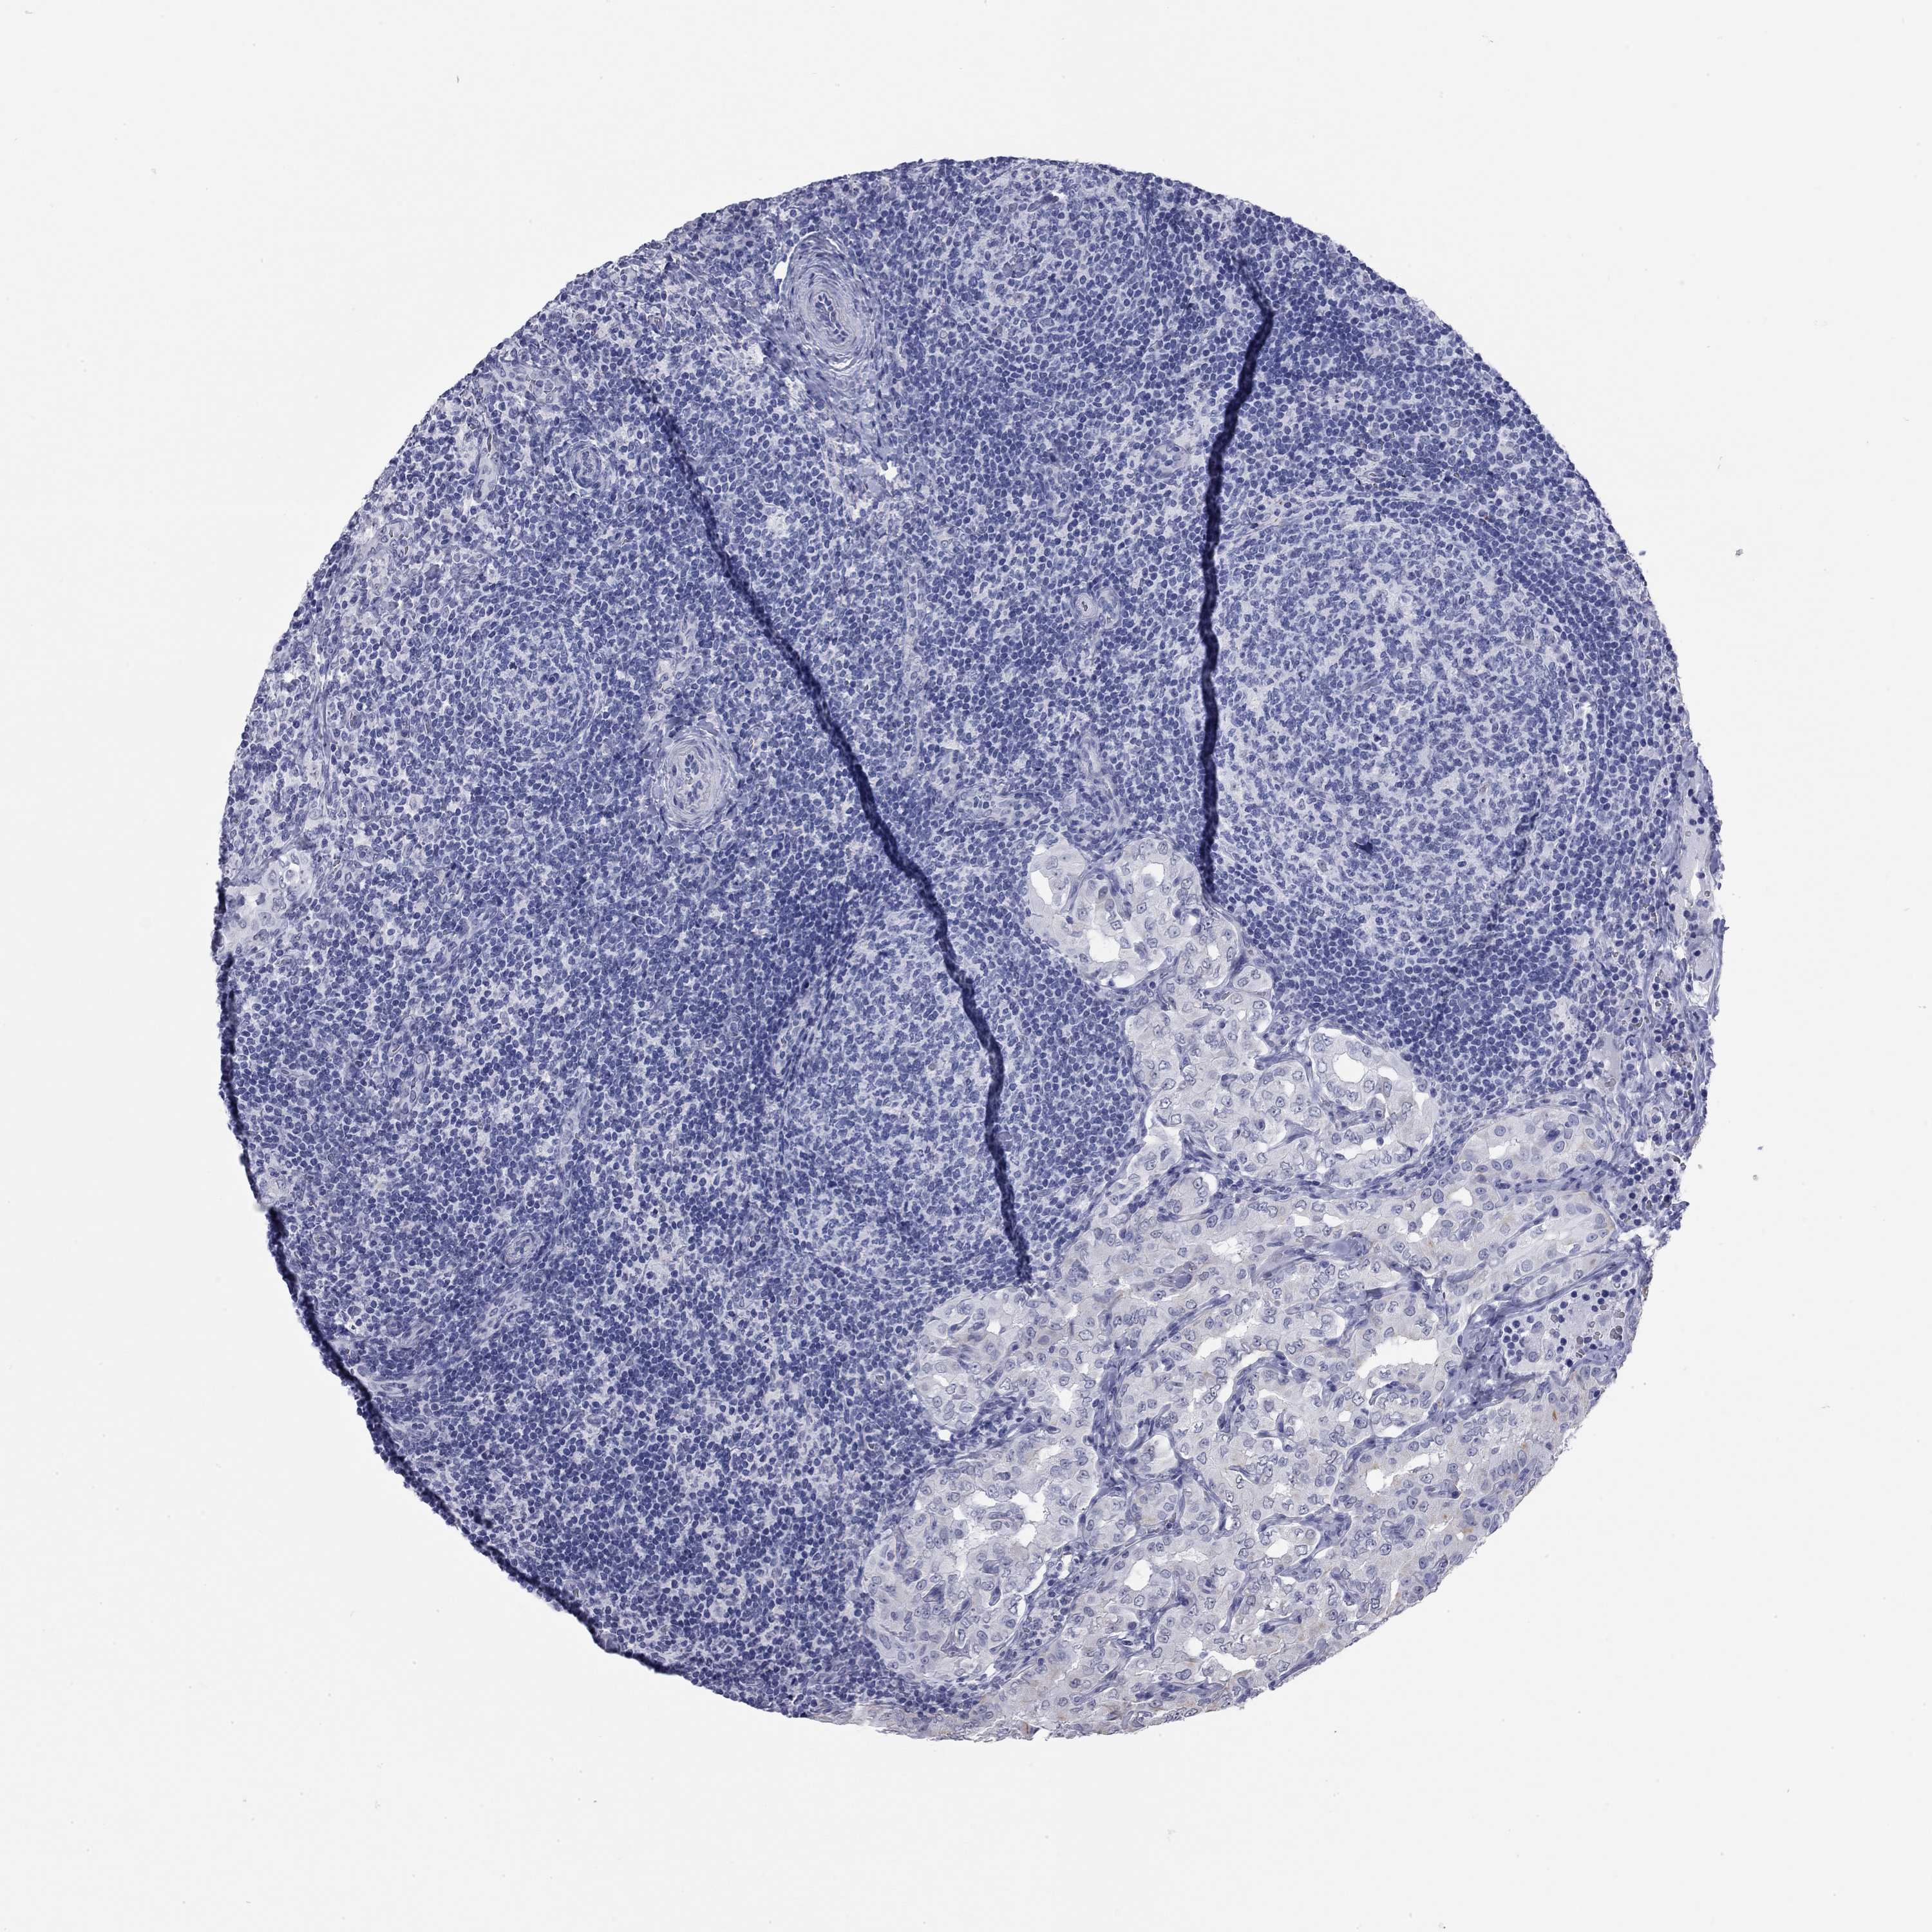

THYROID CANCER - Protein expressioni

A mouse-over function shows sample information and annotation data. Click on an image to view it in a full screen mode. Samples can be filtered based on level of antibody staining by selecting one or several of the following categories: high, medium, low and not detected. The assay and annotation is described here.

Note that samples used for immunohistochemistry by the Human Protein Atlas do not correspond to samples in the TCGA dataset.

Antibody stainingi

Antibody staining in the annotated cell types in the current human tissue is reported as not detected, low, medium, or high, based on conventional immunohistochemistry profiling in selected tissues. This score is based on the combination of the staining intensity and fraction of stained cells.

Each image is clickable and will lead to virtual microscopy that enables deeper exploration of all samples and also displays staining intensity scores, fraction scores and subcellular localization as well as patient and tissue information for each sample.

Antibody HPA021443

Antibody HPA023894

Staining

High

Medium

Low

Not detected

Intensity

Strong

Moderate

Weak

Negative

Quantity

>75%

75%-25%

<25%

None

Location

Nuclear

Cytoplasmic/membranous

Cytoplasmic/membranous,nuclear

Papillary adenocarcinoma, NOS

Follicular adenoma carcinoma, NOS